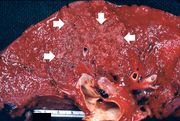

| 04:14, 19 August 2013 | IPLab3ChronicPepticUlcer1.jpg (file) | 58 KB | Seung Park | This is a gross photograph of a stomach containing an ulcer. Note the folded pink gastric mucosa that extends up to the edge of the ulcer (arrows). | 1 | |